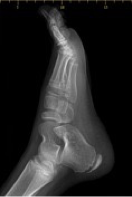

clubfeet/talipes equinovarus

what condition?

talipes equinovarus

clubfeet is also called ________________

adductus

varus

equinus (limited dorsiflexion)

positioning of club feet/talipes equinovarus:

forefoot ____________

hindfoot ____________

ankle ______________